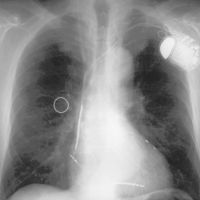

Herzschrittmacher-Implantation, -Aggregatwechsel, -Revision

Herzschrittmacher stellen für eine Reihe von bradykarden Herzrhythmusstörungen, d.h. Rhythmusstörungen, die mit einer zu niedrigen Herzfrequenz einhergehen, eine sichere und relativ einfach durchzuführende Therapieoption dar. In der Regel ist ein Herzschrittmacher dann indiziert, wenn die Bradykardie zu Symptomen wie z.B. Bewusstlosigkeit (Synkope) führt. Die Funktion des Herzschrittmachers ist es, in diesen Fällen den herzeigenen Rhythmus wahrzunehmen und bei Unterschreiten einer bestimmten Herzfrequenz das Herz zu stimulieren.

Die Gründe für die Revision oder Explantation eines Herzschrittmachers sind vielfältig. Bei Problemen am Herzschrittmacheraggregat kann es sich z.B. um eine Fehlfunktion handeln. Aber auch Infektionen, Perforationen und ähnliche Komplikationen treten in seltenen Fällen auf. Bei den Sonden können Komplikationen wie z.B. Sondenbruch oder Sondendislokation die Schrittmacherfunktion beeinträchtigen. Infektionen und Perforationen von Sonden sind sehr selten. Häufige Revisionen können auf Mängel bei den Implantationsoperationen hinweisen.